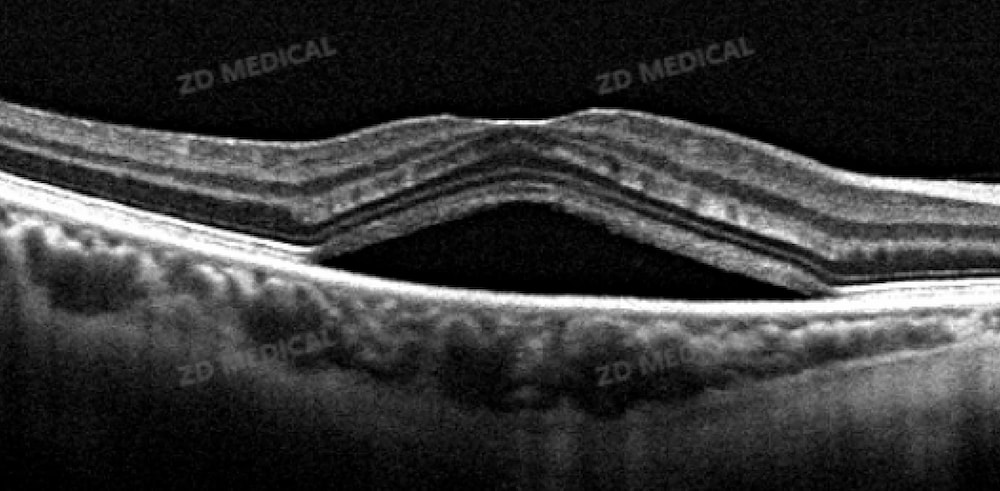

The fundus, as the core hub for visual signal transmission, often serves as an "early warning" for blindness due to its microscopic lesions. Traditional examination methods are difficult to capture the subtle changes between retinal layers. However, OCT technology has achieved a breakthrough by virtue of its unique advantage of "optical biopsy" - through the principle of weak coherent light interference, it can reconstruct two-dimensional and three-dimensional images of the fundus with millimeter-level depth and micrometer-level resolution Clearly present key lesion markers such as intraretinal effusion (IRF) and subretinal effusion (SRF).

The core technology adopted by ZD Medical OCT can complete a full retinal scan within 3 seconds, and the image resolution is 40% higher than that of traditional equipment. Even the tiny protrusions in the retinal pigment epithelial layer of early-stage AMD patients can be accurately captured. The built-in AI+ remote film reading function of the device, along with online review by retinal disease experts, covers all ophthalmic diseases. This effectively empowers primary medical institutions, breaks through the limitations of time, space and resources, standardizes diagnostic results, reduces the occurrence of missed and misdiagnoses, and minimizes clinical risks to the greatest extent. As emphasized in the "2025 Expert Consensus on OCT in the Fundus of China", OCT's ability to identify early lesions far exceeds that of traditional color fundus photography, and the positive screening rate is significantly higher, thus buying precious time for preventing blindness.